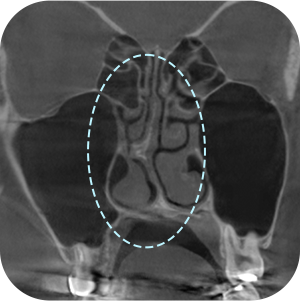

以前、手術の 保形物情報確認

鼻中隔湾曲症など 機能的問題確認

現在の保形物の 位置確認

鼻のCT撮影、どうしても必要ですか?

A再手術ですので、もっと精密に診断する必要があります。

内部の機能的な問題を正確に診断することで

安全な手術が可能となります。

鼻再手術は徹底した分析が重要です。

3D-CTを通じて正確な分析が

できるから! - 03